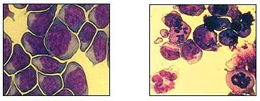

Leukaemia cells before (left) and after (right) the induction of caspase-independent apoptosis. Apoptotic morphology includes cell shrinkage, chromatin condensation, nuclear fragmentation and the formation of apoptotic bodies.

However, despite these advances drug target identification and new drug design is limited due to an incomplete knowledge of the core cell death machinery. In the past decade research into cell death mechanisms has focussed on caspases, a family of cysteine proteases activated during apoptosis. In recent years however, increasing evidence of programmed cell death in the absence of caspase activity has led to the hypothesis that a variety of cell death programmes may be triggered in distinct circumstances and interdependence of these programmes is required in order to complete the cell death process. Triggering caspase-independent death pathways has become an attractive alternative approach to eradicating tumour cells although it is less well understood and many questions regarding the identity of pathway components remain unanswered. The existence of alternative cell death programmes implies novel therapeutic targets and biomarkers for disease diagnosis and classification.

Using a molecular biology and proteomic approach, we are investigating the involvement of novel apoptogenic proteins during caspase-independent apoptosis in a variety of human tumour cells including MCF-7 breast carcinoma cells and chronic myeloid leukaemia (CML) cells. Deciphering the molecular components of these alternative cascades will provide valuable information that is the key to the design of a new generation of targeted drugs.